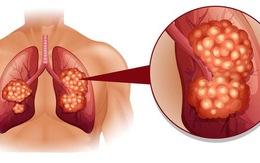

Ung thư phổi là nguyên nhân hàng đầu gây tử vong do ung thư: Người bị ung thư phổi sống được bao lâu?

Với các phương pháp điều trị tiên tiến hiện nay đã kéo dài đáng kể thời gian sống thêm của các bệnh nhân ung thư phổi tế bào nhỏ, tuy nhiên vẫn là thách thức với nhiều bệnh nhân.

Ung thư phổi tiên lượng xấu nếu phát hiện muộn: Chỉ cần có dấu hiệu này là phải khám ngay!

Mặc dù là căn bệnh đứng đầu trong nhóm bệnh ung thư, nhưng số lượng người tự phát hiện bệnh trong giai đoạn sớm để đi khám là không cao. Đây là dấu hiệu nhắc bạn cần vào viện ngay.

8 biểu hiện không ngờ tới của ung thư phổi: Hãy cảnh giác!

Nên nhớ rằng, hãy đến bệnh viện ngay lập tức nếu bản thân phát hiện bất cứ dấu hiệu nghi ngờ nào, bởi điều trị chỉ có thể thành công nếu bệnh được phát hiện ở giai đoạn sớm.